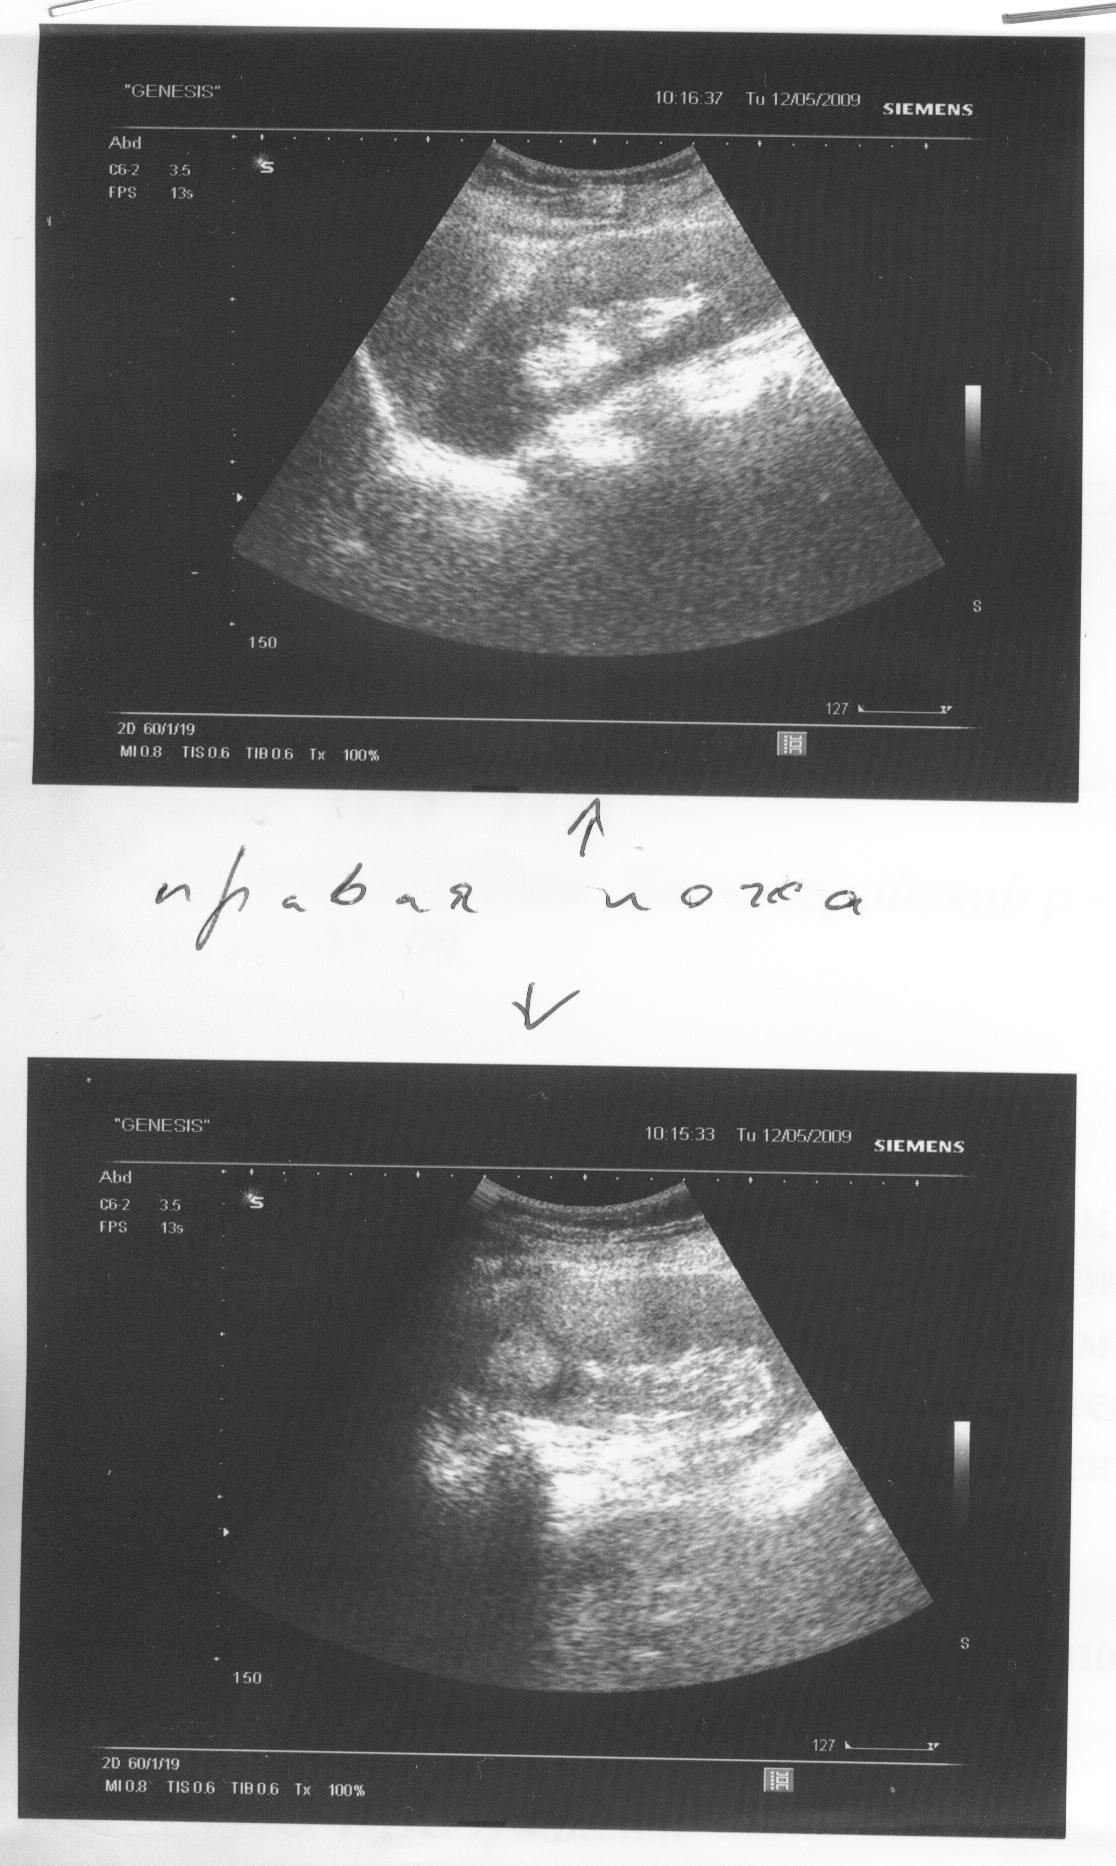

Здравствуйте! У мамы в 2002г. была операция по удалению почки со злокачественной опухолью. В результате обследования УЗИ совсем недавно(май 2009) было обнаружено образование на другой почке, затем сделали КТ - размер образования (около верхнего полюса) 32x26 мм. Врачи (в том числе профессор) говорят, что гарантий по операции дать не могут, поскольку почка единственная и большой риск кровопотери. Сами говорят, что выхода нет и чтобы думали быстро. Мама операцию делать не хочет. Я знаю случаи, когда люди жили недолго (год-два) после проведенных операций. Как Вы считаете стоит ли рискнуть? Сколько в среднем люди живут после проведенной резекции единственной почки? Помогите пожалуйста советом.

Прикреплены файлы -- исследования УЗИ и текст от КТ.

Мы внимательно ознакомились с представленными результатами исследований.

В данном случае предпочтительным является резекция единственной правой почки. Количество осложнений, которые могут сопутствовать любому хирургическому вмешательству зависят от многих параметров: опыта врача и количество выполненных подобных операций, технического оснащения и т.п.

Опухоль располагается в верхнем сегменте (полюсе) почки поэтому резекция почки имеет свои особенности, но ни в коем случае не должна обуславливать пассивную выжидательную тактику. Если у Вас остаются сомнения, проконсультируйтесь у нас очно для возможности выполнения резекции почки на базе в Москве.